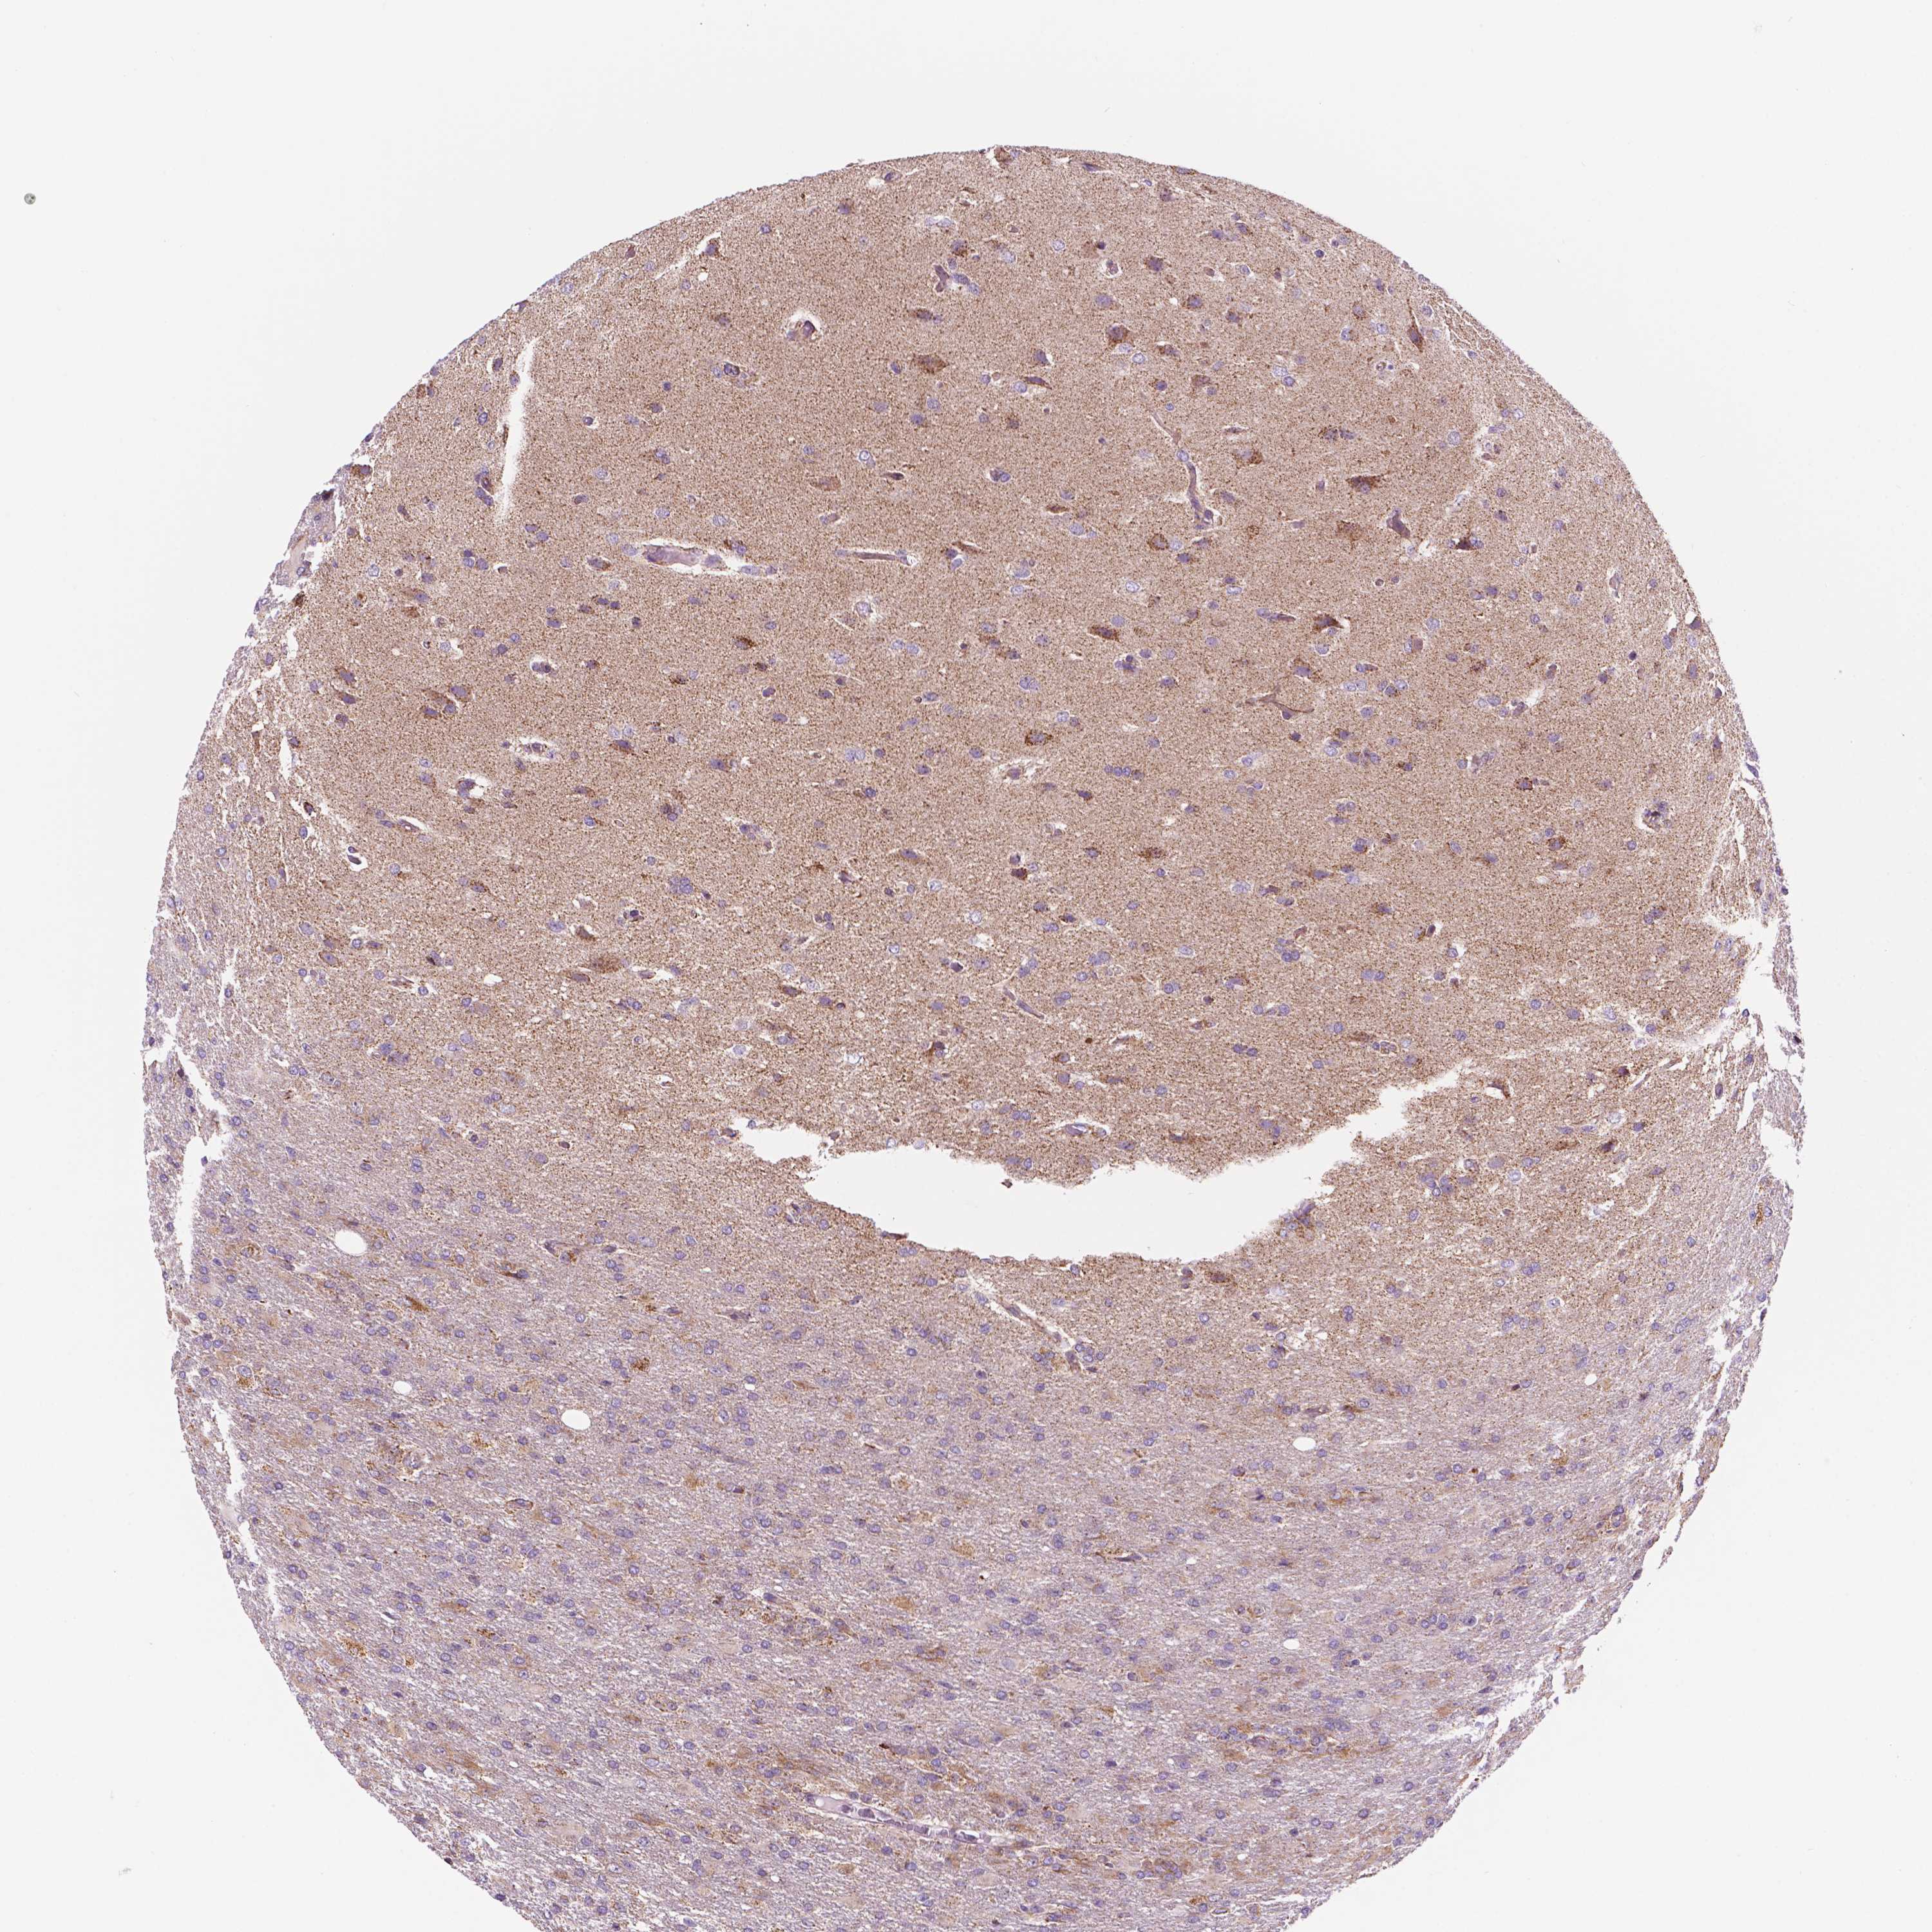

GLIOMA - Protein expressioni

A mouse-over function shows sample information and annotation data. Click on an image to view it in a full screen mode. Samples can be filtered based on level of antibody staining by selecting one or several of the following categories: high, medium, low and not detected. The assay and annotation is described here.

Note that samples used for immunohistochemistry by the Human Protein Atlas do not correspond to samples in the TCGA dataset.

Antibody stainingi

Antibody staining in the annotated cell types in the current human tissue is reported as not detected, low, medium, or high, based on conventional immunohistochemistry profiling in selected tissues. This score is based on the combination of the staining intensity and fraction of stained cells.

Each image is clickable and will lead to virtual microscopy that enables deeper exploration of all samples and also displays staining intensity scores, fraction scores and subcellular localization as well as patient and tissue information for each sample.

Antibody HPA067891

Staining

High

Medium

Low

Not detected

Intensity

Strong

Moderate

Weak

Negative

Quantity

>75%

75%-25%

<25%

None

Location

Nuclear

Cytoplasmic/membranous

Cytoplasmic/membranous,nuclear

Glioma, malignant, Low grade

Glioma, malignant, High grade

Glioma, malignant, NOS